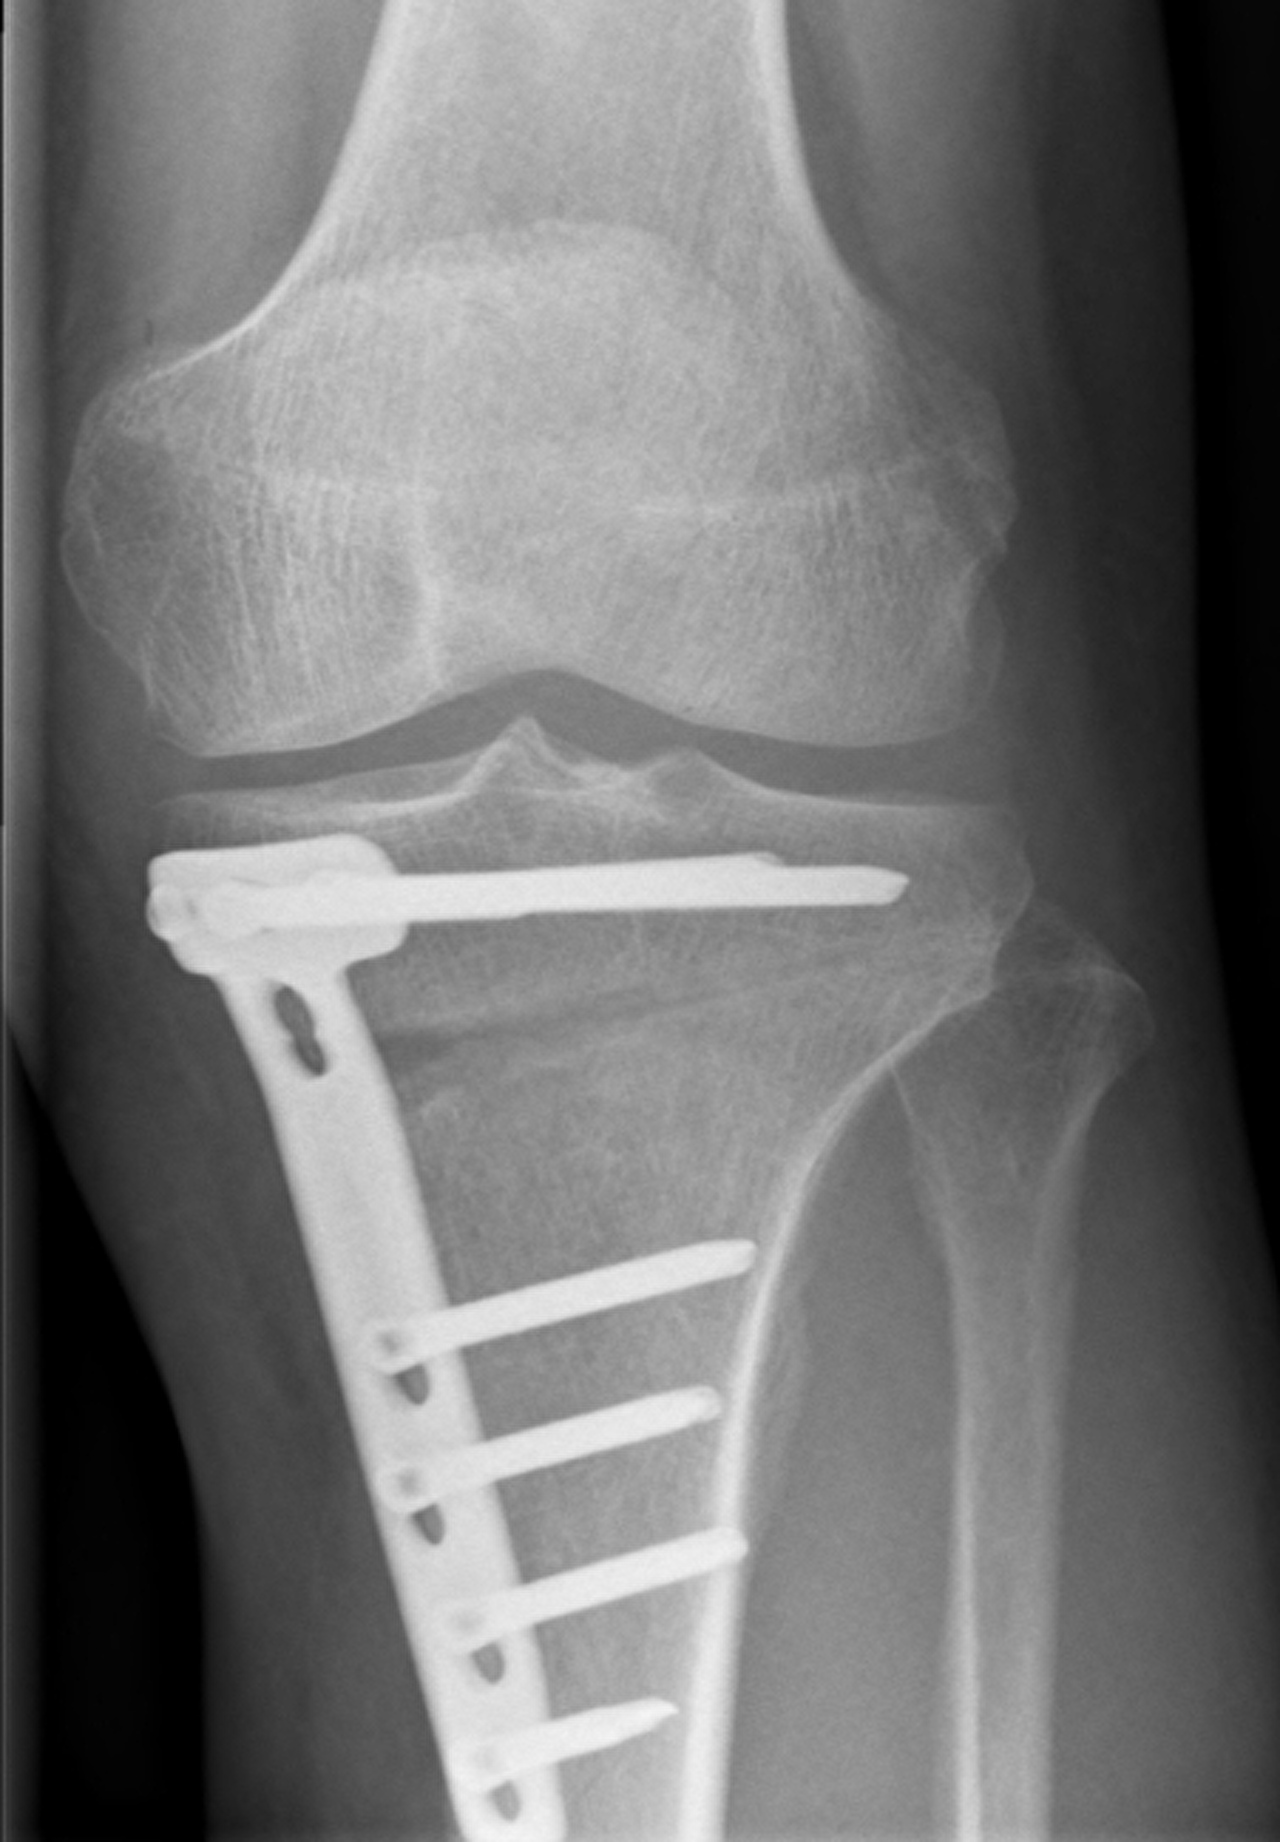

Röntgenfoto vooraanzicht knie na tibiakop osteotomie.

Fixatie door middel van plaat en schroeven.

Open wig-techniek.